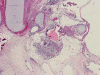

The excised specimen consists of multiple fragments of tan, soft tissue, 5.0 x 2.0 x 1.0 cm in aggregate, for examination. On gross examination, neither calcified tissue nor hair were found. An intraoperative frozen section and cytologic preparation was performed which revealed mature intestinal element, skin and small amount of hair. No germinoma element, yolk sac tumor (endodermal sinus tumor) element, embryonal cell carcinoma, or immature teratoma component was present in multiple specimens submitted for frozen section. Although a minute amount of hair was revealed on the frozen section, gross examination of the submitted tissue does not identify any hair or calcified tissue. An intraoperative diagnosis of teratoma with only mature element present was made.

The entire specimen was submitted for histologic examination. The bulk (over 99%) of the tumor was composed predominantly of mature intestinal elements (Panel A, B, and C) and skin, respiratory type mucosa, cartilage, and small amount of mature neural parenchymal tissue of the central nervous system (Panel D and E). Neither immature nor malignant elements are present. Small microscopic foci of well demarcated, neural parenchymal tissue with increased atypia (arrow in panel F) are noted. On higher magnification (Panel G and H), these areas contain large, bizarre appearing cells with dark chromatin but no prominent nucleoli. There are also scant multinucleated cells and mineralized substances (arrow in Panel H). Another example of these foci is illustrated in Panel I, J, and K. These atypical foci comprised less than 1% of the volume of the tumor. They are all microscopic in size and show no evidence of expansion or invasion into the surrounding tissue.

The foci of neural parenchymal tissue with atypia raised the concern for malignancy. The atypical foci are all microscopic in size and well demarcated. They do not invade into the adjacent tissue. Although large atypical nuclei are noted, there is no prominent nucleoli. These changes are more consistent with ancient changes (degenerative atypia) or resulted from the chemotherapy prior to the resection. Identification of mineralized tissue is an additional features to confirm the benign biological potential of these foci. These foci are atypical but not embryonal and must be distinguished from immature element. With this token, the tumor is a mature teratoma but not an immature teratoma. Please see the discussion below for growing teratoma syndrome. This case is also unusual for an elevated alpha fetal-protein in serum with a lack of yolk sac tumor component in the tumor. Please see the discussion below for discussion.